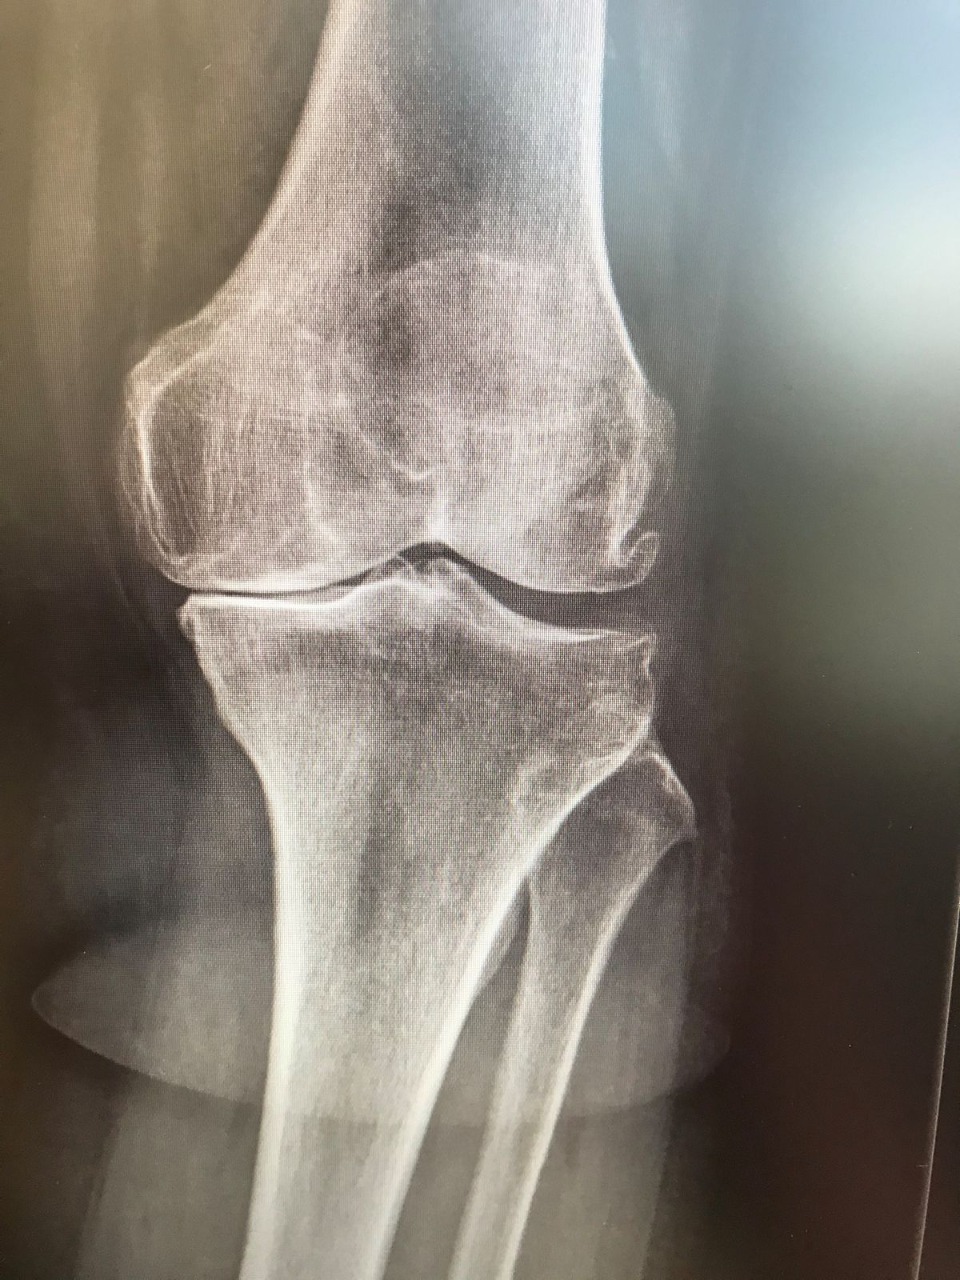

Στην πλειοψηφία των ασθενών με οστεοαρθρίτιδα του γόνατος, η παθολογία περιορίζεται στο έσω διαμέρισμα αυτού (περίπου 50%). Το γόνατο έχει τρία διαμερίσματα: το έσω, το έξω και το πρόσθιο. Πρακτικά, η οστεοαρθρίτιδα μπορεί να προσβάλλει οποιοδήποτε από τα τρία διαμερίσματα του γόνατος. Εάν η οστεοαρθρίτιδα περιορίζεται σε ένα μόνο από τα τρία αυτά διαμερίσματα, μπορούμε να επιλέξουμε ως τεχνική τη μονοδιαμερισματική αρθροπλαστική.

Ειδικότερα, η Μονοδιαμερισματική Αρθροπλαστική Γόνατος (ΜΑΓ) είναι μία καθιερωμένη θεραπευτική επιλογή για γόνατα που πάσχουν από αρθρίτιδα σε ένα μόνον τμήμα τους (εικ. 1) και αποτελείται από τρία μέρη: Από το μηριαίο τμήμα, το οποίο κατασκευάζεται από μέταλλο, από μια μεταλλική βάση, η οποία τοποθετείται πάνω στην κνήμη, και ανάμεσα τους υπάρχει ένα πλαστικό, κινούμενο τμήμα (πολυαιθυλένιο) (εικ. 2).